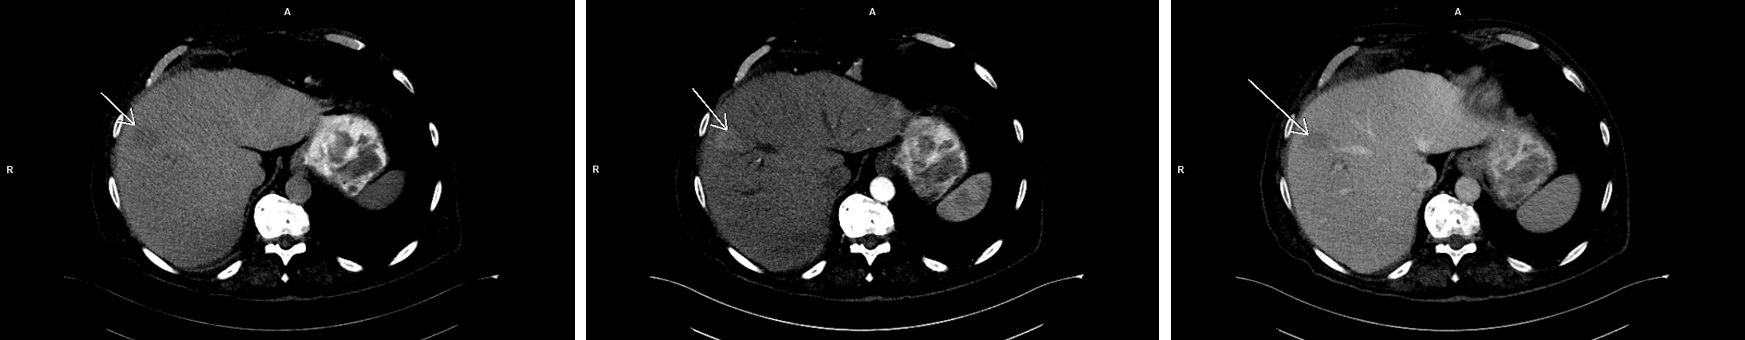

Figura 1: axial CT nativ, timp arterial și timp venos

Pacientul era cunoscut cu polipoza adenomatoasă și i s-a descoperit întâmplător la ecografie o leziune expansivă hepatică. Pe examinarea CT nu a putut fi caracterizat convenabil iar la examinarea IRM s-a decelat o leziune spontan în hipersemnal T1 cu priză de contrast în timp precoce și fenomen de spălare rapidă a contrastului în timp venos / tardiv.